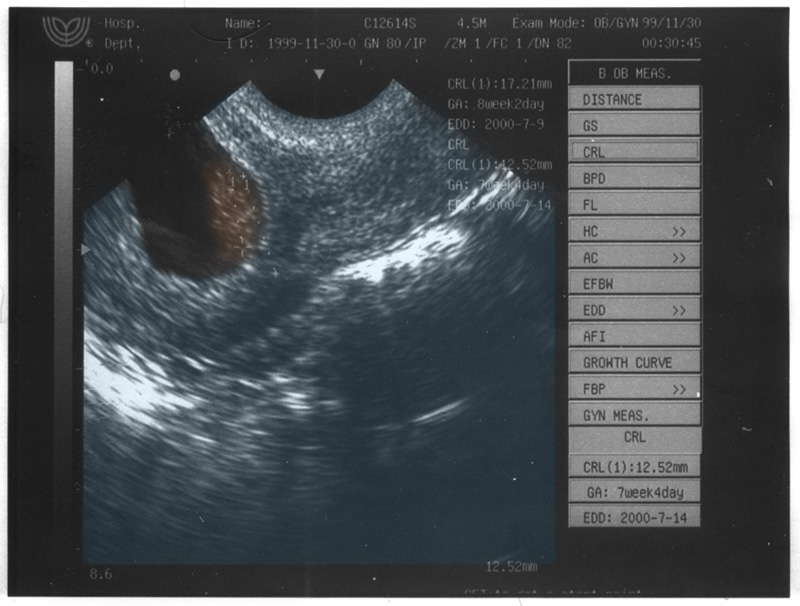

Last time in trying to color the ultrasound, I just ended up making the kid look like a turd, but now they both do. Here's Vienna's: